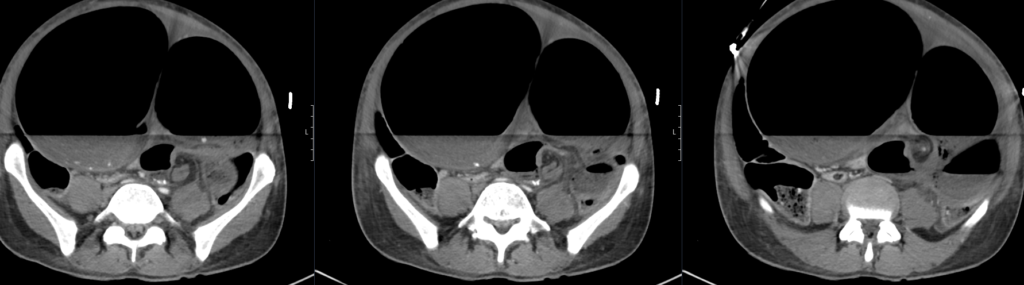

A CT mesenteric angiogram is urgently arranged.

CT mesenteric angiogram

There is evidence of a sigmoid volvulus.

The proximal large bowel as well as small bowel loops are dilated suggestive of an incompetent ileocaecal valve.

There is no pneumoperitoneum to suggest hollow viscus perforation.

There is a moderate volume of free fluid. No collection.

The distended bowel compresses the liver and displaces the gallbladder and spleen posteriorly.

The abdominal aorta as well as the origins of the common iliac arteries and external iliac arteries are compressed by dilated bowel loops however remain patent and there is satisfactory flow distally to the common femoral and superficial femoral arteries.

Comment: Acute sigmoid volvulus with severe bowel obstruction. The dilated bowel loops are significantly compressing the abdominal aorta and pelvic arteries as above. Urgent surgical review recommended.